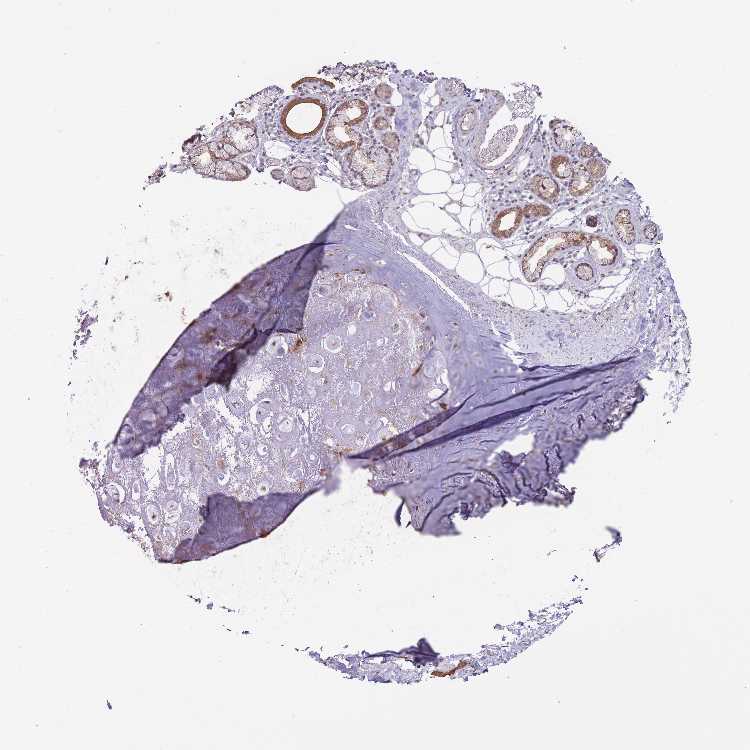

SOFT TISSUE 2 - Antibody stainingi

Antibody staining in the annotated cell types in the current human tissue is reported as not detected, low, medium, or high, based on conventional immunohistochemistry profiling in selected tissues. This score is based on the combination of the staining intensity and fraction of stained cells.

Each image is clickable and will lead to virtual microscopy that enables deeper exploration of all samples and also displays staining intensity scores, fraction scores and subcellular localization as well as patient and tissue information for each sample.

Antibody HPA042733Antibody CAB037186

Fibroblasts Not detectedNot detected